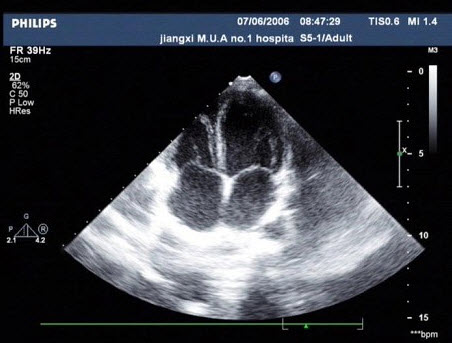

5、单项选择题

该病例最可能诊断()

A.真性动脉瘤

B.假性动脉瘤

C.夹层动脉瘤

D.以上都不是

E.主动脉瓣狭窄